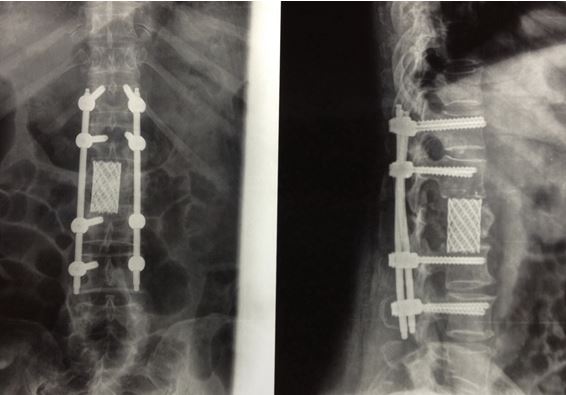

Спондилит – крайне тяжелая патология. Зачастую к врачу пациенты попадают в уже запущенной форме, когда нет возможности адекватно восстановить пораженные структуры. Такие случаи требуют хирургического лечения, которое подразумевает:

- фиксацию пораженного сегмента через небольшие разрезы с целью уменьшения болевого синдрома;

- санацию гнойного очага и замещение его, как протезами, так и специальными биоимплантами.

Такие процедуры позволяют восстановить поврежденные инфекцией костные структуры и вернуться к привычному образу жизни в кратчайшие сроки.

Центр травматологии и ортопедии имеет огромный опыт лечения подобных заболеваний и применяет в лечении современные технологии, в том числе Российских и зарубежных компаний, чья продукция давно зарекомендовала себя на международном и отечественном рынке медицинской продукции.